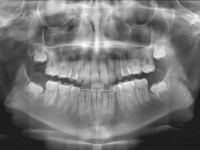

La paciente O.O. acude a nuestra consulta por:

– Canino 13 e incisivo lateral 42 en posición ectópica.

– Canino 23 incluido.

Con lo que decide realizarse un tratamiento de ortodoncia de duración de 24 meses con brackets damon Q.

CASO COMPLETO: